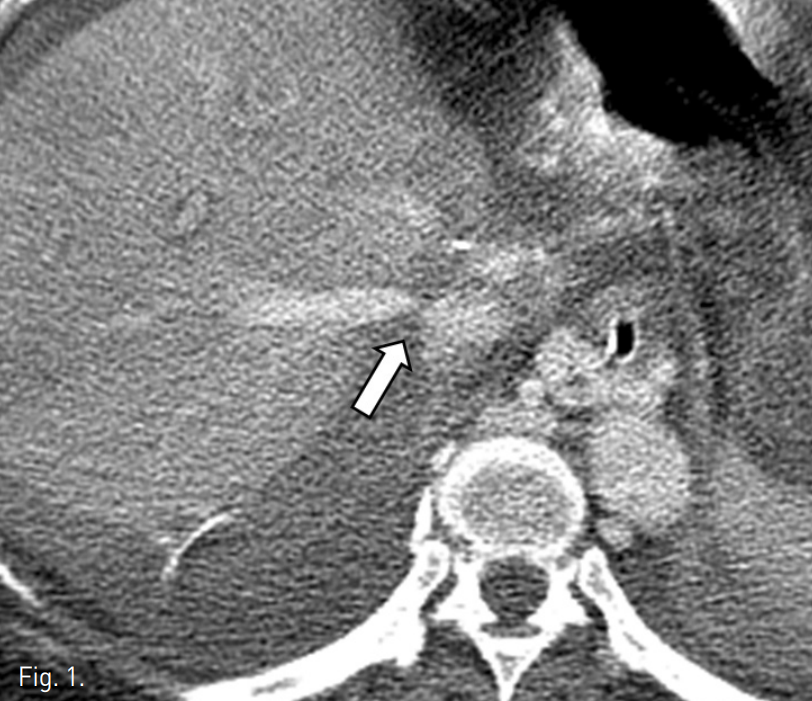

Zilver 스텐트 (Cook, Bloomington, U.S.A)를 삽입하였다(Fig. 3). 스텐트 삽입 후 측정한 pressure gradient는 4mmHg로 감소되었으며 정맥조영술에서 협착은 보이지 않았다. 시술 직후 통증이나 활력 징후의 변화와 같은 합병증은 관찰되지 않았다. 시술 다음날 시행한 color doppler 검사에서 오른간정맥의 spectral waveform이 triphasic하게 관찰되었으며 추적 검사에서도 동일한 소견이 관찰되었다. 시술 후 시행한 CT angiography에서 스텐트는 이전 CT에서 보였던 협착된 부위에 삽입되어 있음을 확인하였고, 스텐

트 내부의 혈전 또는 꼬임 등 이상소견은 보이지 않았다(Fig. 4). 환자는 보존적 치료 후 퇴원하였다.

Fig. 4

Follow-up CT scan shows widely patent stent lumen (arrow).